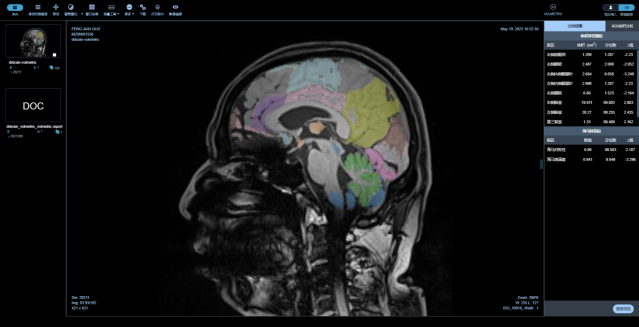

醫(yī)未腦醫(yī)生Dr.Brain

中樞神經(jīng)系統(tǒng)核磁影像AI診斷分析平臺(tái)

是專注在中樞神經(jīng)系統(tǒng)疾病的人工智能診斷分析平臺(tái),基于醫(yī)未自行搭建的全年齡段中國(guó)人群全腦結(jié)構(gòu)影像數(shù)據(jù)庫(kù),結(jié)合前沿的大數(shù)據(jù)分析和人工智能等核心技術(shù),快速、精準(zhǔn)評(píng)估全腦結(jié)構(gòu)變化、腦白質(zhì)病變、微出血灶及腦血流量等,以量化、直觀的結(jié)果,輔助臨床做出超早期的精準(zhǔn)診斷及疾病進(jìn)展預(yù)測(cè)。

最全面的分區(qū)

最全面的腦結(jié)構(gòu)分區(qū),快速獲取全腦100個(gè)精細(xì)腦區(qū)共165項(xiàng)指標(biāo),精度達(dá)到毫米級(jí)